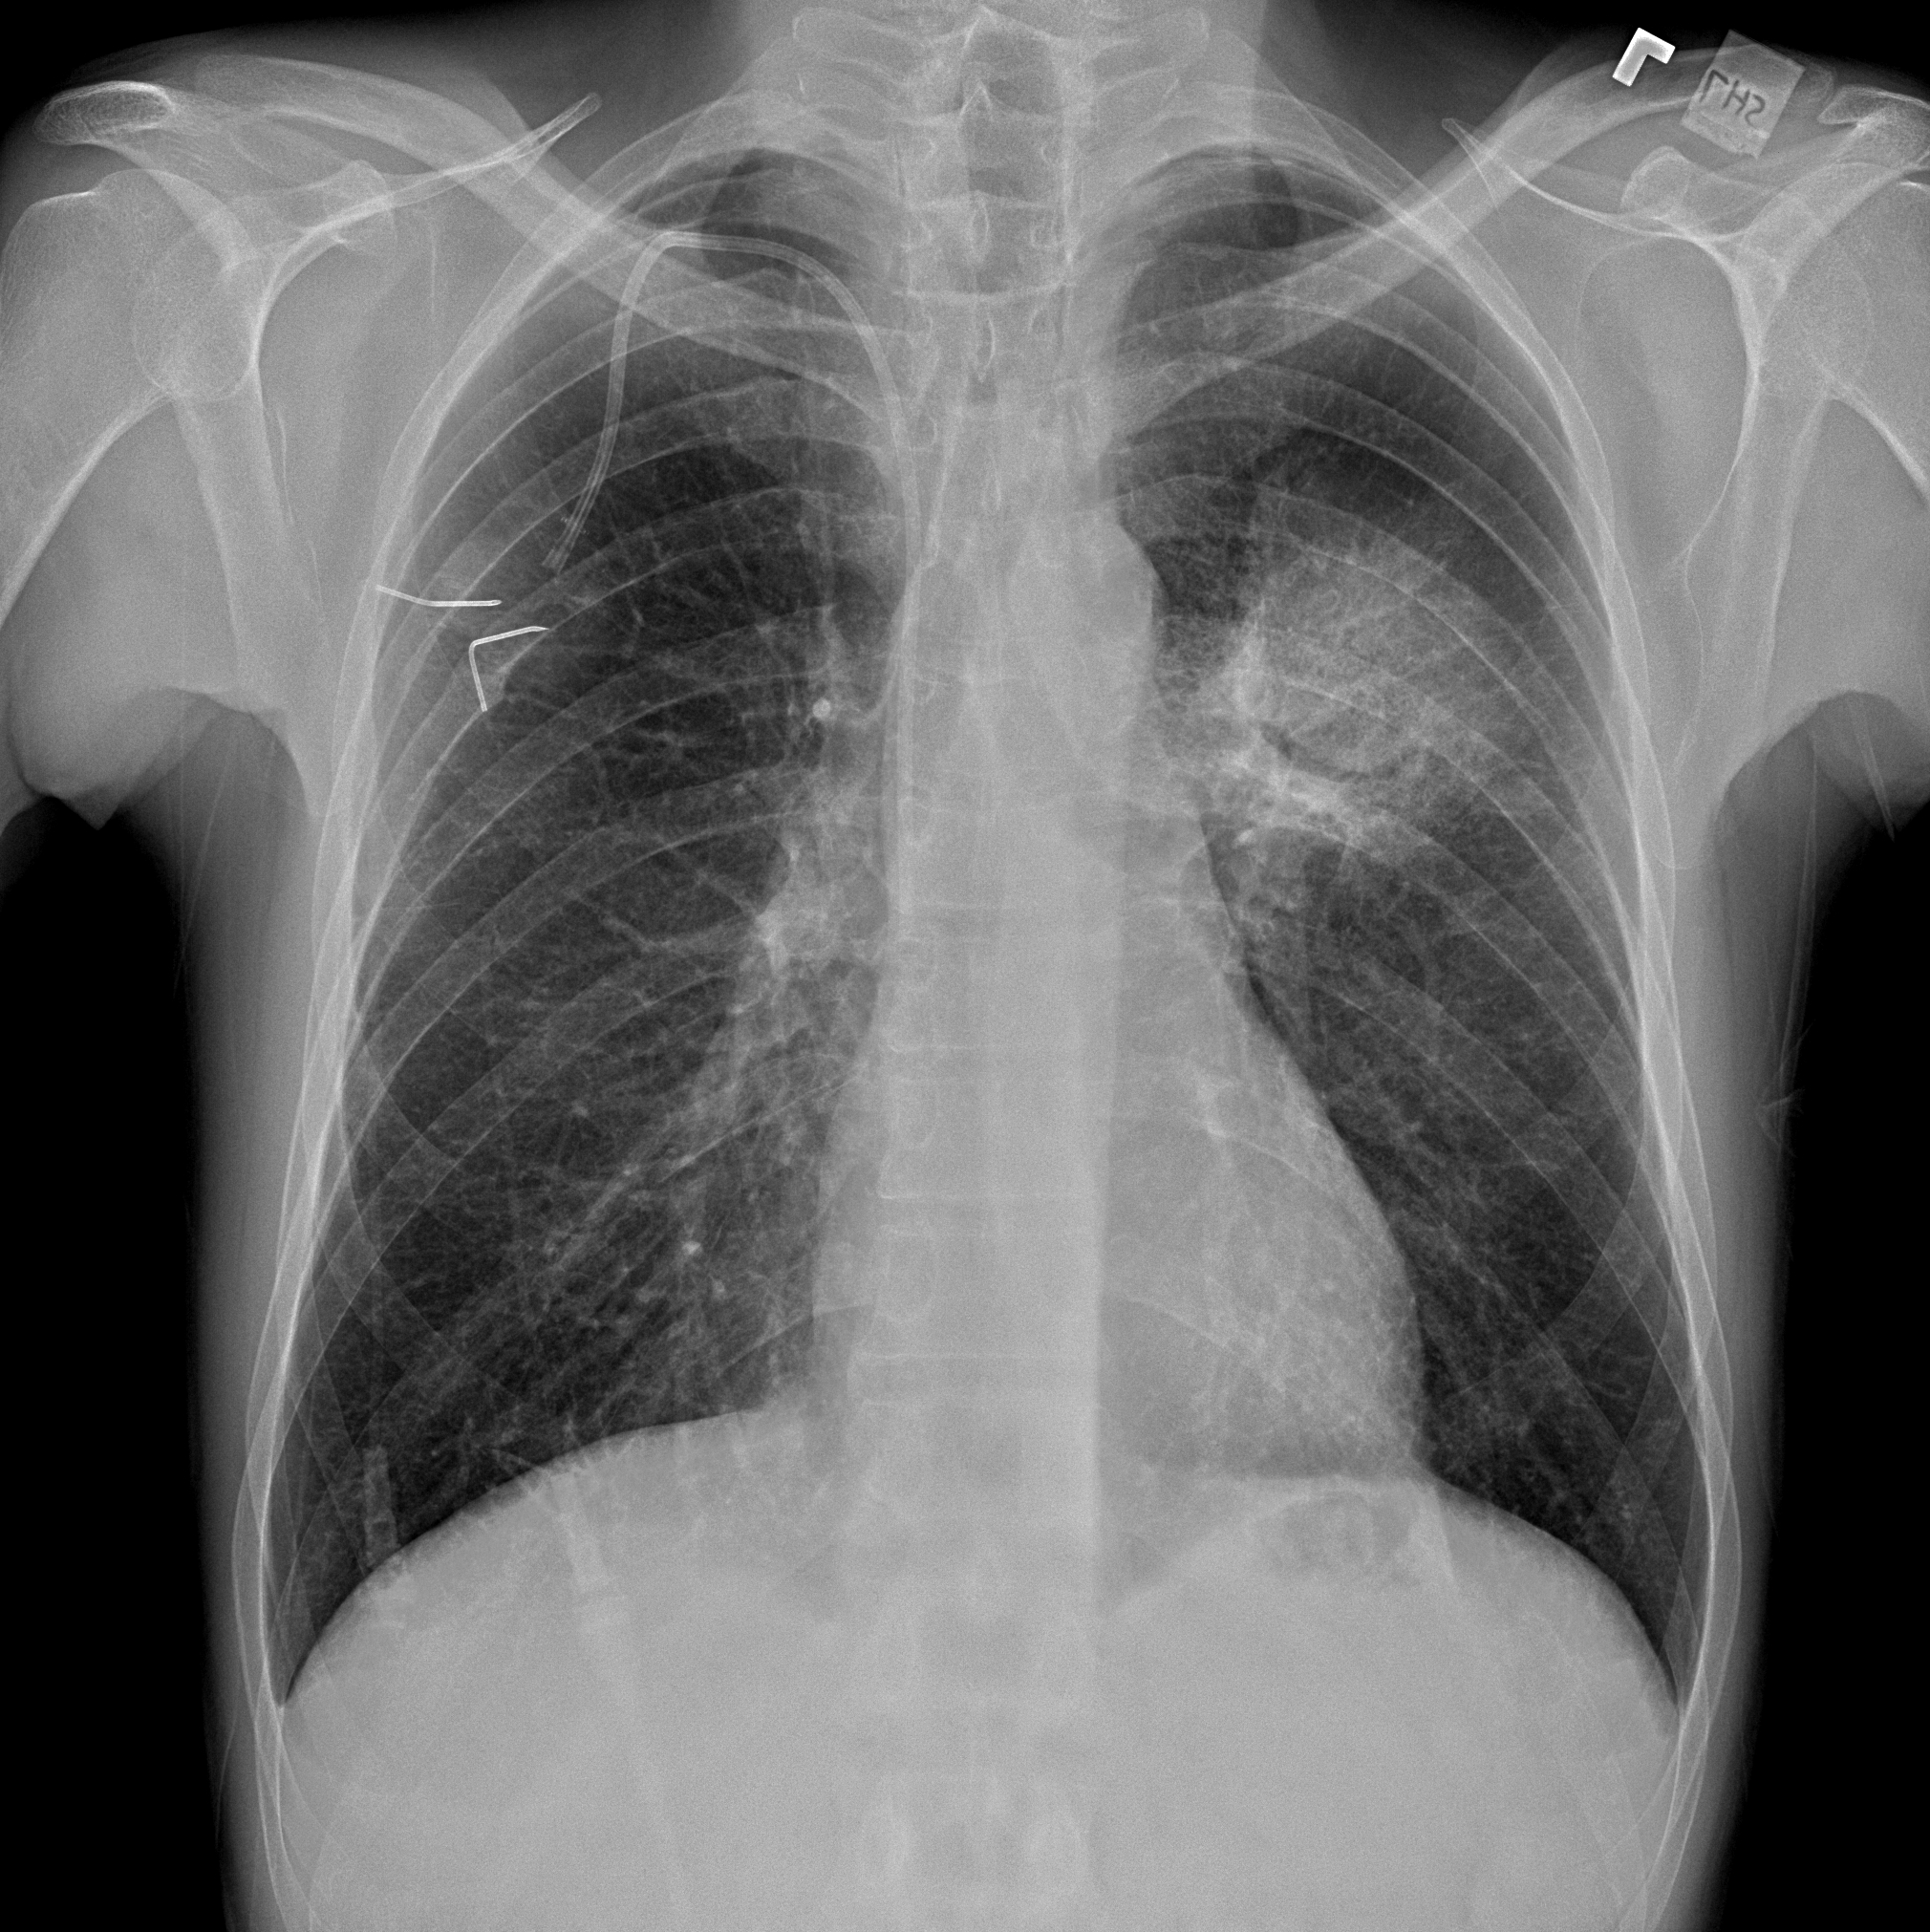

Practice Cases